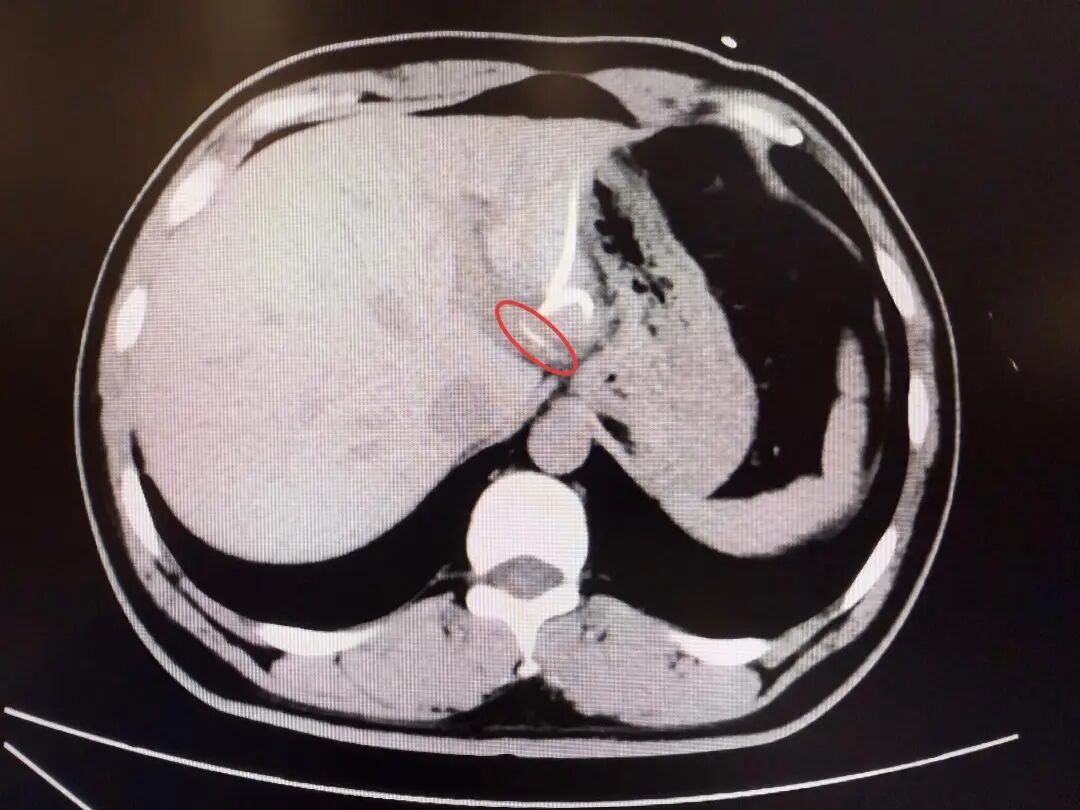

直到行CT检查时,医生才惊讶地发现——肝脏左叶靠近胃贲门处,竟有一条细长的高密度影,形似鱼刺。原来,那根鱼刺在吞咽后穿透了胃壁,从贲门区域“钻”入肝脏,引发感染与脓肿。在简单进行肝脓肿介入穿刺引流后,当地外科医生评估后认为,要彻底清除异物,需要进行左半肝切除手术,但这对于李先生来说,创伤大、风险高,他难以接受。

为寻求更精准、微创的治疗,经当地内镜医生介绍后李先生辗转来到复旦大学附属中山医院内镜中心。“鱼刺位置非常凶险,就在贲门旁刺入左肝,紧贴大血管。”接诊的周平红主任介绍,“病程长、腹腔感染粘连严重,术中可能找不到鱼刺,一旦操作不慎也会造成内镜下无法控制的大出血。”周主任提出了个大胆的设想——能否通过胃镜,在食道管壁夹层建个隧道“开一扇门”,直接进入腹腔取出鱼刺?这个想法意味着要让内镜“跨越”胃壁的天然边界,是一次前所未有的尝试。术前,周平红主任带领内镜团队按照术前CT检查,反复推演每一步操作路径,力求安全与精准兼顾,在手术开始前由团队蔡明琰副主任医师进行超声内镜精准定位,为建立黏膜下隧道指明方向。